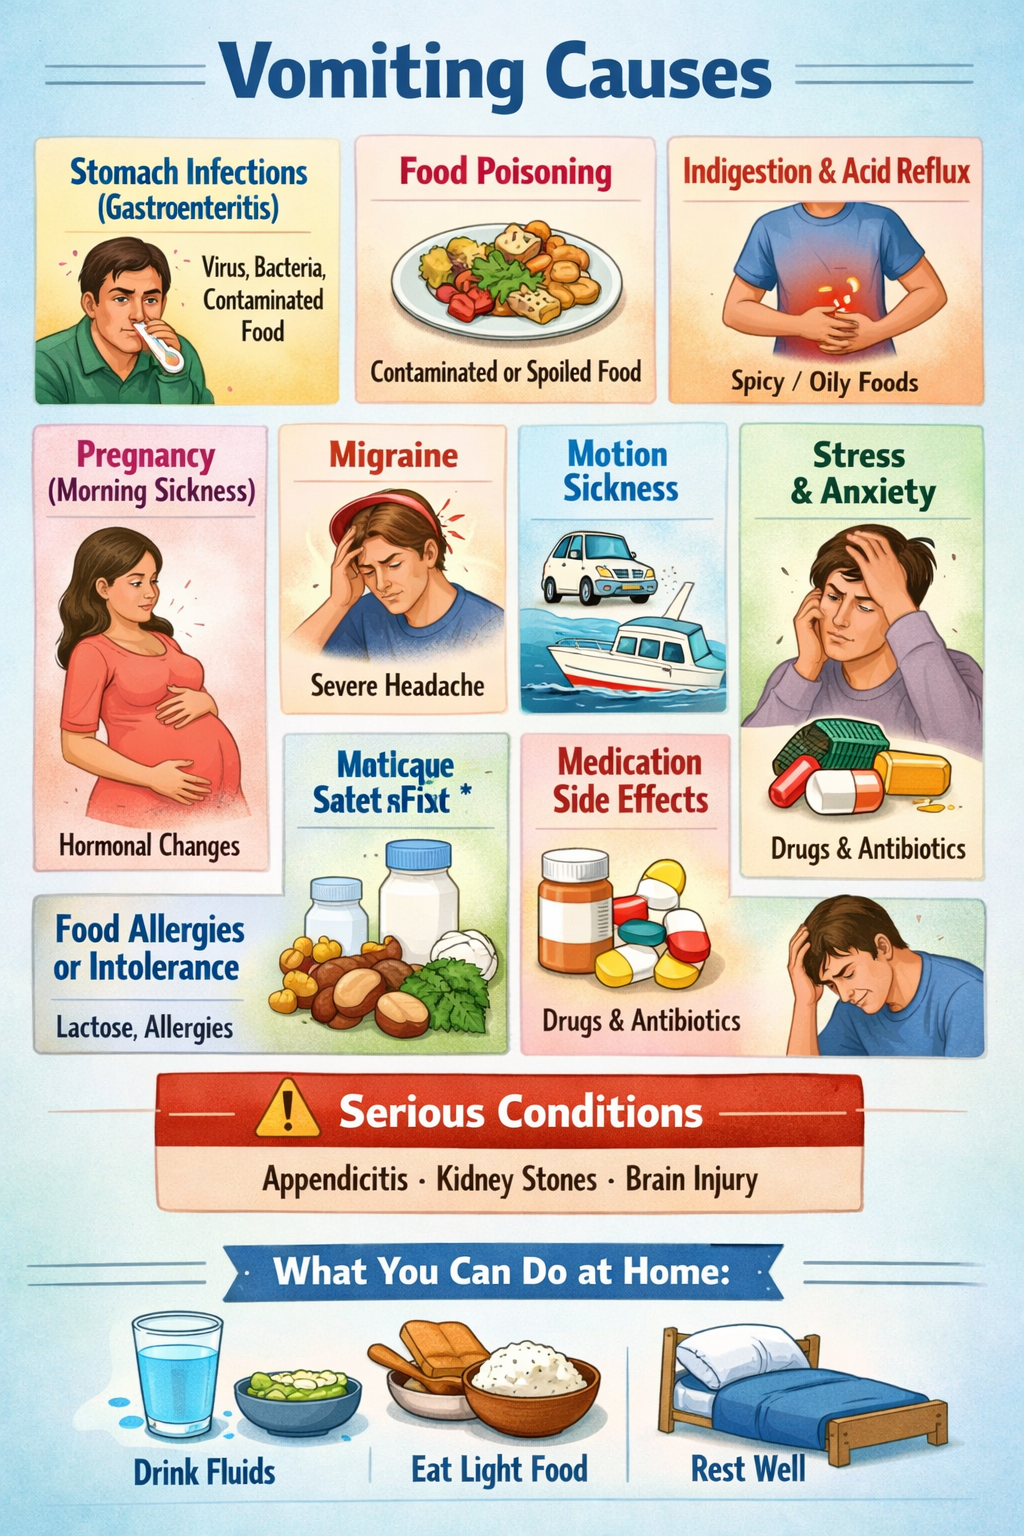

Symptoms of Hepatitis C

In many cases, symptoms are mild or absent during the early stages. When symptoms do occur, they may include:

Chronic fatigue

Nausea and vomiting

Loss of appetite

Abdominal pain

Dark urine

Jaundice (yellowing of skin and eyes)

Swelling in legs or abdomen (advanced disease)

Early diagnosis significantly improves treatment success.